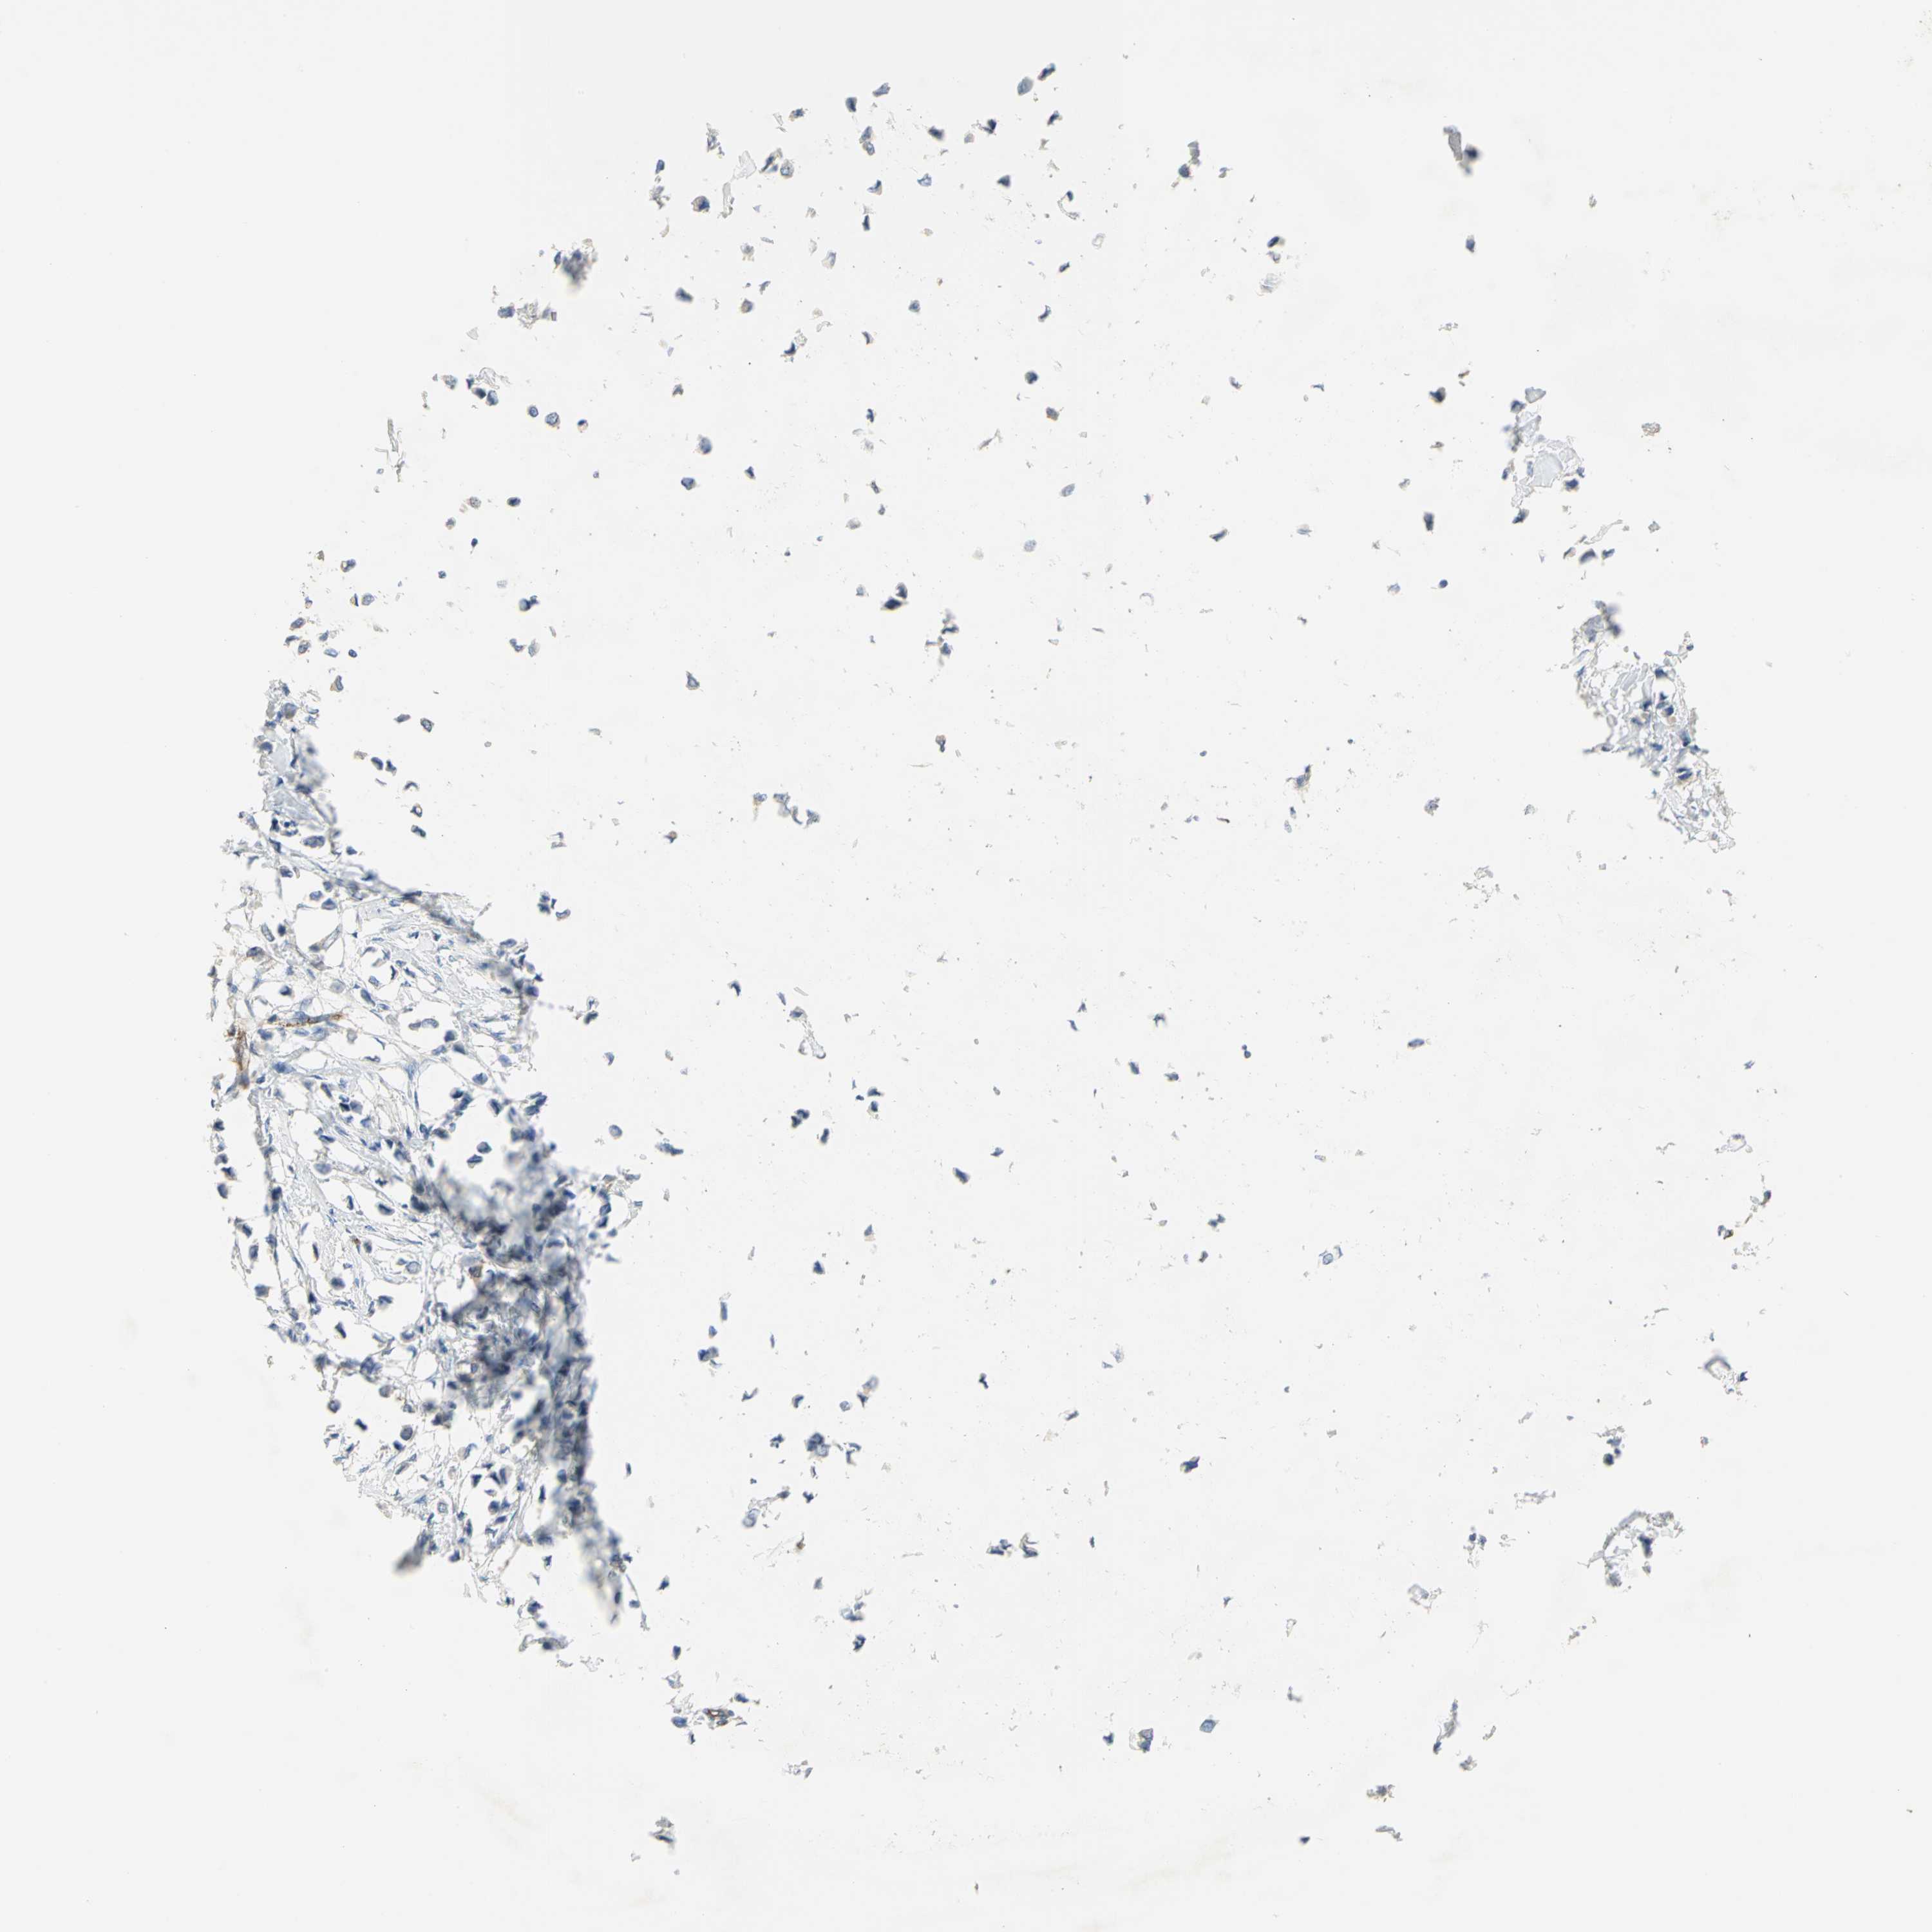

CANCER BREAST CANCER Show tissue menu

BRCA TCGA BRCA VALIDATION PROTEIN EXPRESSION

DLGAP5 is not prognostic in Breast Invasive Carcinoma (TCGA)